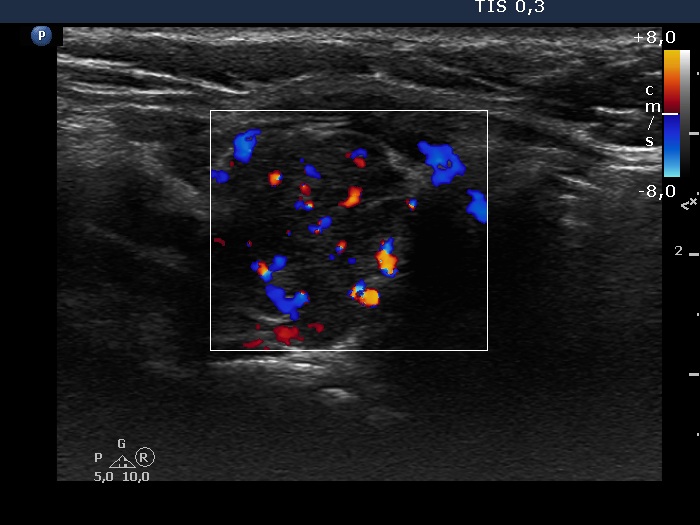

Consecutive patients with the final diagnosis of Hashimoto's thyroiditis - case 60 (1383) (ultrasonographic picture 8)

Lower part of the left lobe, longitudinal scan, color Doppler mode. The vascularization is increased.